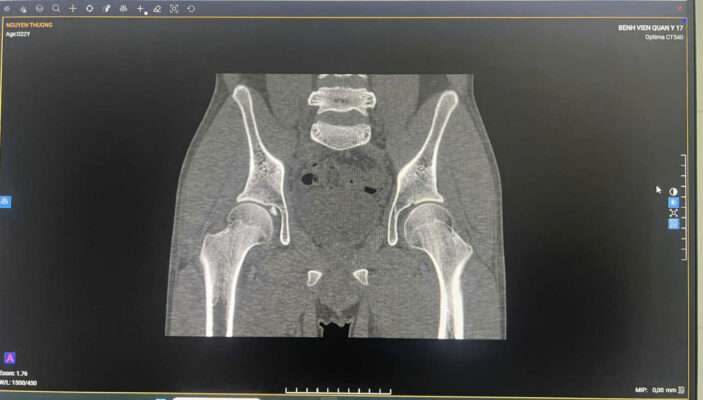

1. MỞ ĐẦU 📚Tổn thương phối hợp giữa dị vật nội khớp háng và mạc giữ bánh chè – đùi trong (Medial Patellofemoral Ligament – MPFL) là tình huống hiếm gặp trong chấn thương chỉnh hình. 👉Các biểu hiện lâm sàng thường không đặc hiệu, dễ bị che lấp bởi triệu chứng đau đa vùng sau chấn thương, dẫn đến nguy cơ bỏ sót tổn thương nội khớp nếu không được đánh giá hình ảnh đầy đủ. 💥Việc phối hợp giữa khám lâm sàng tỉ mỉ và chẩn đoán hình ảnh chuyên sâu (CT, MRI) đóng vai trò quyết định trong việc phát hiện sớm, định hướng điều trị và tiên lượng phục hồi chức năng vận động cho người bệnh. 2. CA LÂM SÀNG 📚 Bệnh nhân nam, sau chấn thương biểu hiện đau vùng háng và gối phải, hạn chế vận động chi dưới cùng bên, đã khám ở BV tuyến trước không xác định được tổn thương. Đêm ngày 03/10, chuyển đến Bệnh viện Quân y 17, qua khám lâm sàng ghi nhận đau sâu vùng háng, đau mặt trong gối khi vận động gấp duỗi, khi sờ ấn, không có biến dạng. 📚Hình ảnh CT scan khớp háng phát hiện một dị vật nhỏ nằm trong ổ khớp háng phải, nghi là mảnh xương vỡ gây kẹt khớp sau chấn thương. MRI khớp gối phải cho thấy tổn thương mạc giữ bánh chè – đùi trong (MPFL) tại chỗ bám vào xương bánh chè, kèm tràn dịch khớp nhẹ. 👉 Nhờ phối hợp chặt chẽ giữa bác sĩ lâm sàng và bác sĩ chẩn đoán hình ảnh, tổn thương phối hợp hiếm gặp này được xác định chính xác, giúp tránh bỏ sót dị vật nội khớp và mô mềm quanh gối khó phát hiện nếu chỉ dựa vào thăm khám. 👉Bệnh nhân được dự kiến lấy dị vật nội khớp háng bằng kỹ thuật ít xâm lấn, nội soi kết hợp màn hình tăng sáng hỗ trợ, bảo tồn mạc giữ khớp bánh chè – đùi trong do không gây di lệch xương bánh chè. 3. BÀN LUẬN 👉 Dị vật nội khớp háng là tổn thương ít gặp, thường thứ phát sau chấn thương gãy xương vùng chậu – ổ cối. Trong khi đó, rách MPFL là tổn thương hay gặp nhất trong trật khớp, gãy xương bánh chè cấp, nhưng hiếm khi xuất hiện đồng thời với dị vật nội khớp háng. Khi hai tổn thương này cùng tồn tại, triệu chứng thường chồng lấp, dễ dẫn đến chẩn đoán không đầy đủ hoặc điều trị chưa triệt để.

✓ Theo Guerrero và cộng sự, MRI là phương tiện hiệu quả nhất để nhận diện tổn thương MPFL và phân loại mức độ rách (tại điểm bám vào bánh chè, tại xương đùi hoặc rách đoạn giữa), trong khi CT giúp phát hiện chính xác các mảnh xương tự do hoặc dị vật trong khớp [3]. ✓ Các tác giả Selmene MA (2022) và Davis ES (2019) cũng khẳng định rằng kỹ thuật lấy dị vật nội khớp háng ít xâm lấn hoặc có hỗ trợ C-arm giúp giảm sang chấn mô mềm và rút ngắn thời gian hồi phục [1],[2]. ✓ Trong báo cáo này, việc phối hợp CT – MRI đã cho phép phát hiện đầy đủ cả hai tổn thương, đồng thời định hướng phẫu thuật hợp lý: lấy dị vật nội khớp nội soi, đồng thời khâu phục hồi cấu trúc mạc giữ khớp bánh chè – đùi trong nếu cần thiết. ✓ Cách tiếp cận này giúp hạn chế nguy cơ bỏ sót tổn thương nhỏ, bảo tồn cấu trúc khớp và phục hồi sớm chức năng vận động. 4. KẾT LUẬN ✓Tổn thương phối hợp giữa dị vật nội khớp háng và rách mạc giữ bánh chè – đùi trong là hiếm gặp và có thể bị bỏ sót nếu không được đánh giá toàn diện. ✓Sự phối hợp chặt chẽ giữa bác sĩ lâm sàng và chẩn đoán hình ảnh là yếu tố then chốt giúp chẩn đoán chính xác, lựa chọn chiến lược điều trị hợp lý, mang lại kết quả phục hồi tối ưu cho người bệnh. 📚Trường hợp tại Bệnh viện Quân y 17 là minh chứng cho năng lực chuyên sâu của đơn vị trong chẩn đoán và xử trí các tổn thương chấn thương chỉnh hình phức tạp, góp phần nâng cao chất lượng điều trị và an toàn người bệnh. 5. TÀI LIỆU THAM KHẢO [1]. Selmene MA, et al. Minimally invasive removal of intra-articular hip fragments. [Journal of Orthopaedic Case Reports]. 2022. [2]. Davis ES, et al. A novel technique to remove posterior intra-articular hip foreign bodies via anterior approach. Tech Orthop. 2019;34(4):302-306. [3]. Guerrero P, Li X, Patel K, Brown M, Busconi BD. Medial patellofemoral ligament injury patterns and associated pathology in lateral patella dislocation: an MRI study. Sports Med Arthrosc Rehabil Ther Technol. 2009;1:17. [4]. Conlan T, Garth WP Jr, Lemons JE. Evaluation of the medial soft tissue restraints of the extensor mechanism of the knee. J Bone Joint Surg Am. 1993;75:682-693. [5]. Nomura E, Inoue M, Osada N. Anatomical analysis of the medial patellofemoral ligament of the knee, especially the femoral attachment. Knee Surg Sports Traumatol Arthrosc. 2005;13:510-515. [6]. Smith A, et al. Medial patellofemoral ligament reconstruction: a systematic review. Orthop J Sports Med. 2024;12(1):1-10.